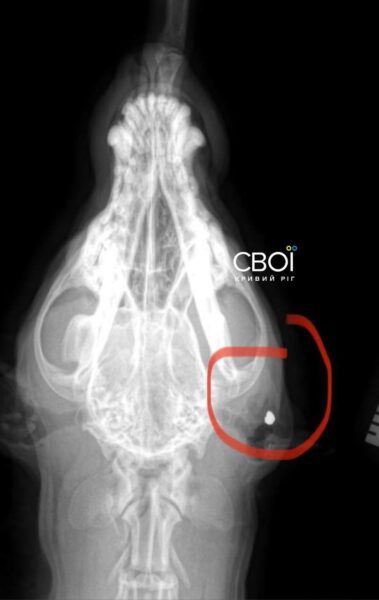

Ветеринар назначил лечение для Бати. Одна из пуль застряла в голове животного, другая — возле желудка. Достать их, чтобы не навредить собаке, невозможно.